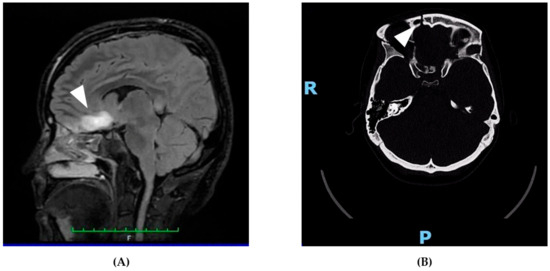

On 21 April 2025, a 31-year-old woman was admitted to the emergency department following a high-impact car accident resulting in multiple traumatic injuries. She had no relevant past medical history and no smoking, alcohol, or substance use habits. She had completed 13 years of education and was employed. At initial evaluation, she appeared alert but partially oriented, exhibiting mild psychomotor agitation while remaining cooperative with medical staff. Whole-body computed tomography (CT) revealed bilateral intraparenchymal cerebral contusions, multiple splanchnocranial fractures with orbital involvement, paraseptal emphysema at the level of the pulmonary hilum, and focal lingual post-contusion consolidation. On 24 April, she was transferred to the neurosurgery department for further maxillofacial, ophthalmologic, and thoracic assessments. On 27 April, during hospitalization, the patient experienced a generalized comitial crisis accompanied by hyponatremia and new-onset anisocoria. Given the temporal proximity to the injury (day 6), the event was classified as an acute symptomatic seizure according to current ILAE criteria. A repeat CT scan showed no acute changes compared to previous imaging. Due to worsening neurological status, she was transferred to the intensive care unit, where she required intubation and underwent a brain MRI (Figure 1). MRI findings demonstrated artifacts consistent with diffuse axonal injury, along with cytotoxic edema involving the pituitary gland and the pericallosal pedicle. Following stabilization, she was extubated on 6 May and underwent a neurological examination. She was awake, cooperative, and able to move all four limbs symmetrically, with no signs of paresis or abnormal posturing. A mild reduction in muscle strength was observed, likely attributable to prolonged immobilization. Pupils were isochoric and reactive to light. Her neurological condition was deemed clinically stable, and she was transferred back to the neurosurgery ward. On 15 May, a maxillofacial examination confirmed consolidation of Craniomaxillofacial Orbitozygomatic (COMZ) fractures. A small, slightly displaced bone fragment persisted in the periorbital region but did not result in functional impairment, as confirmed by a subsequent ophthalmological evaluation. The patient nonetheless reported a persistent foreign body sensation and pain during ocular movements, likely due to impingement of the displaced fragment on the oblique ocular muscle. Given her progressive medical stabilization, on 21 May 2025, the patient was transferred to the IRCCS Maugeri Institute for post-acute intensive neurorehabilitation (see Table 2 for Clinical Case Overview).

Figure 1. Representative neuroimaging findings following severe traumatic brain injury. (A) Sagittal FLAIR MRI showing a hyperintense lesion in the pericallosal region and pituitary stalk, consistent with diffuse axonal injury and cytotoxic edema. These findings support the neuroanatomical basis for the patient’s cognitive, executive, and neuroendocrine symptoms. (B) Axial non-contrast CT scan revealing a right orbitozygomatic complex fracture with disruption of the orbital wall, consistent with the patient’s initial ocular motility impairment and diplopia. This image demonstrates the extent of craniofacial trauma sustained at the time of injury. The MRI images are original and were obtained as part of the patient’s routine clinical assessment. All images were fully anonymized, and written informed consent for publication was obtained. No copyright permission is required.